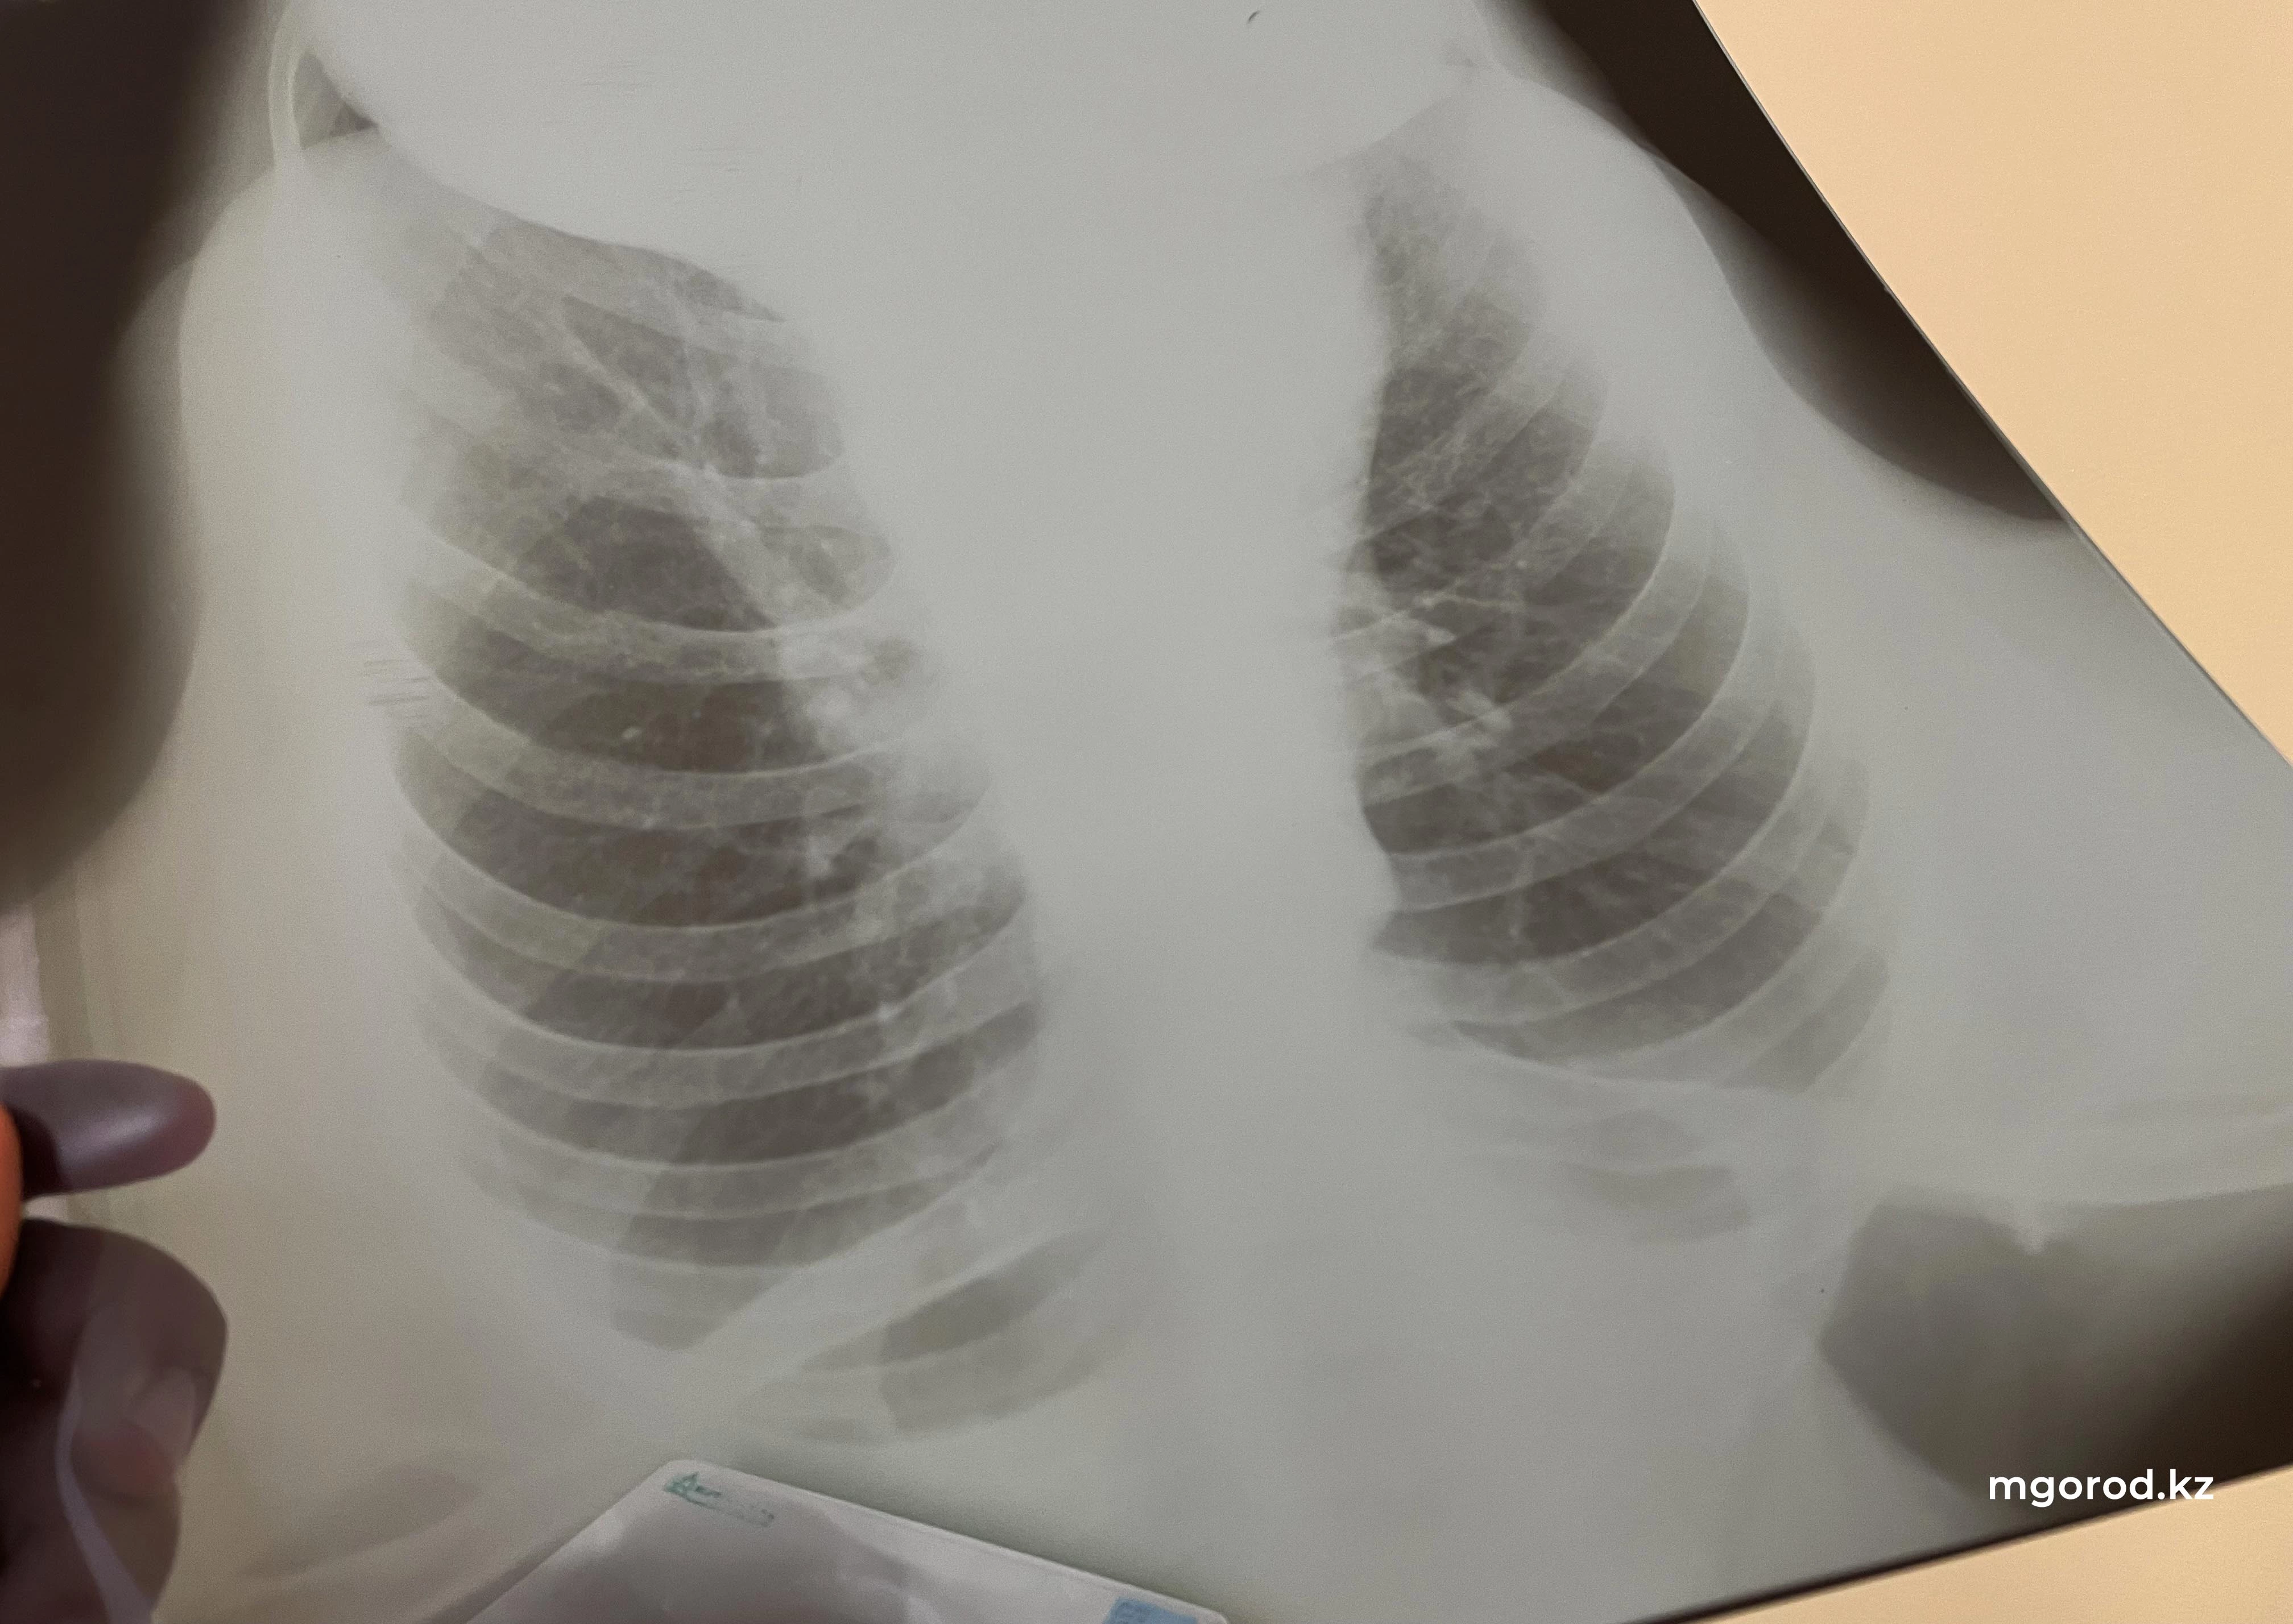

— Ждем всех желающих, вне зависимости от статуса застрахованности в системе ОСМС бесплатно пройти все методы выявления туберкулеза (тест GeneXpert, рентген снимок, результаты анализов), — сообщили в ведомстве.